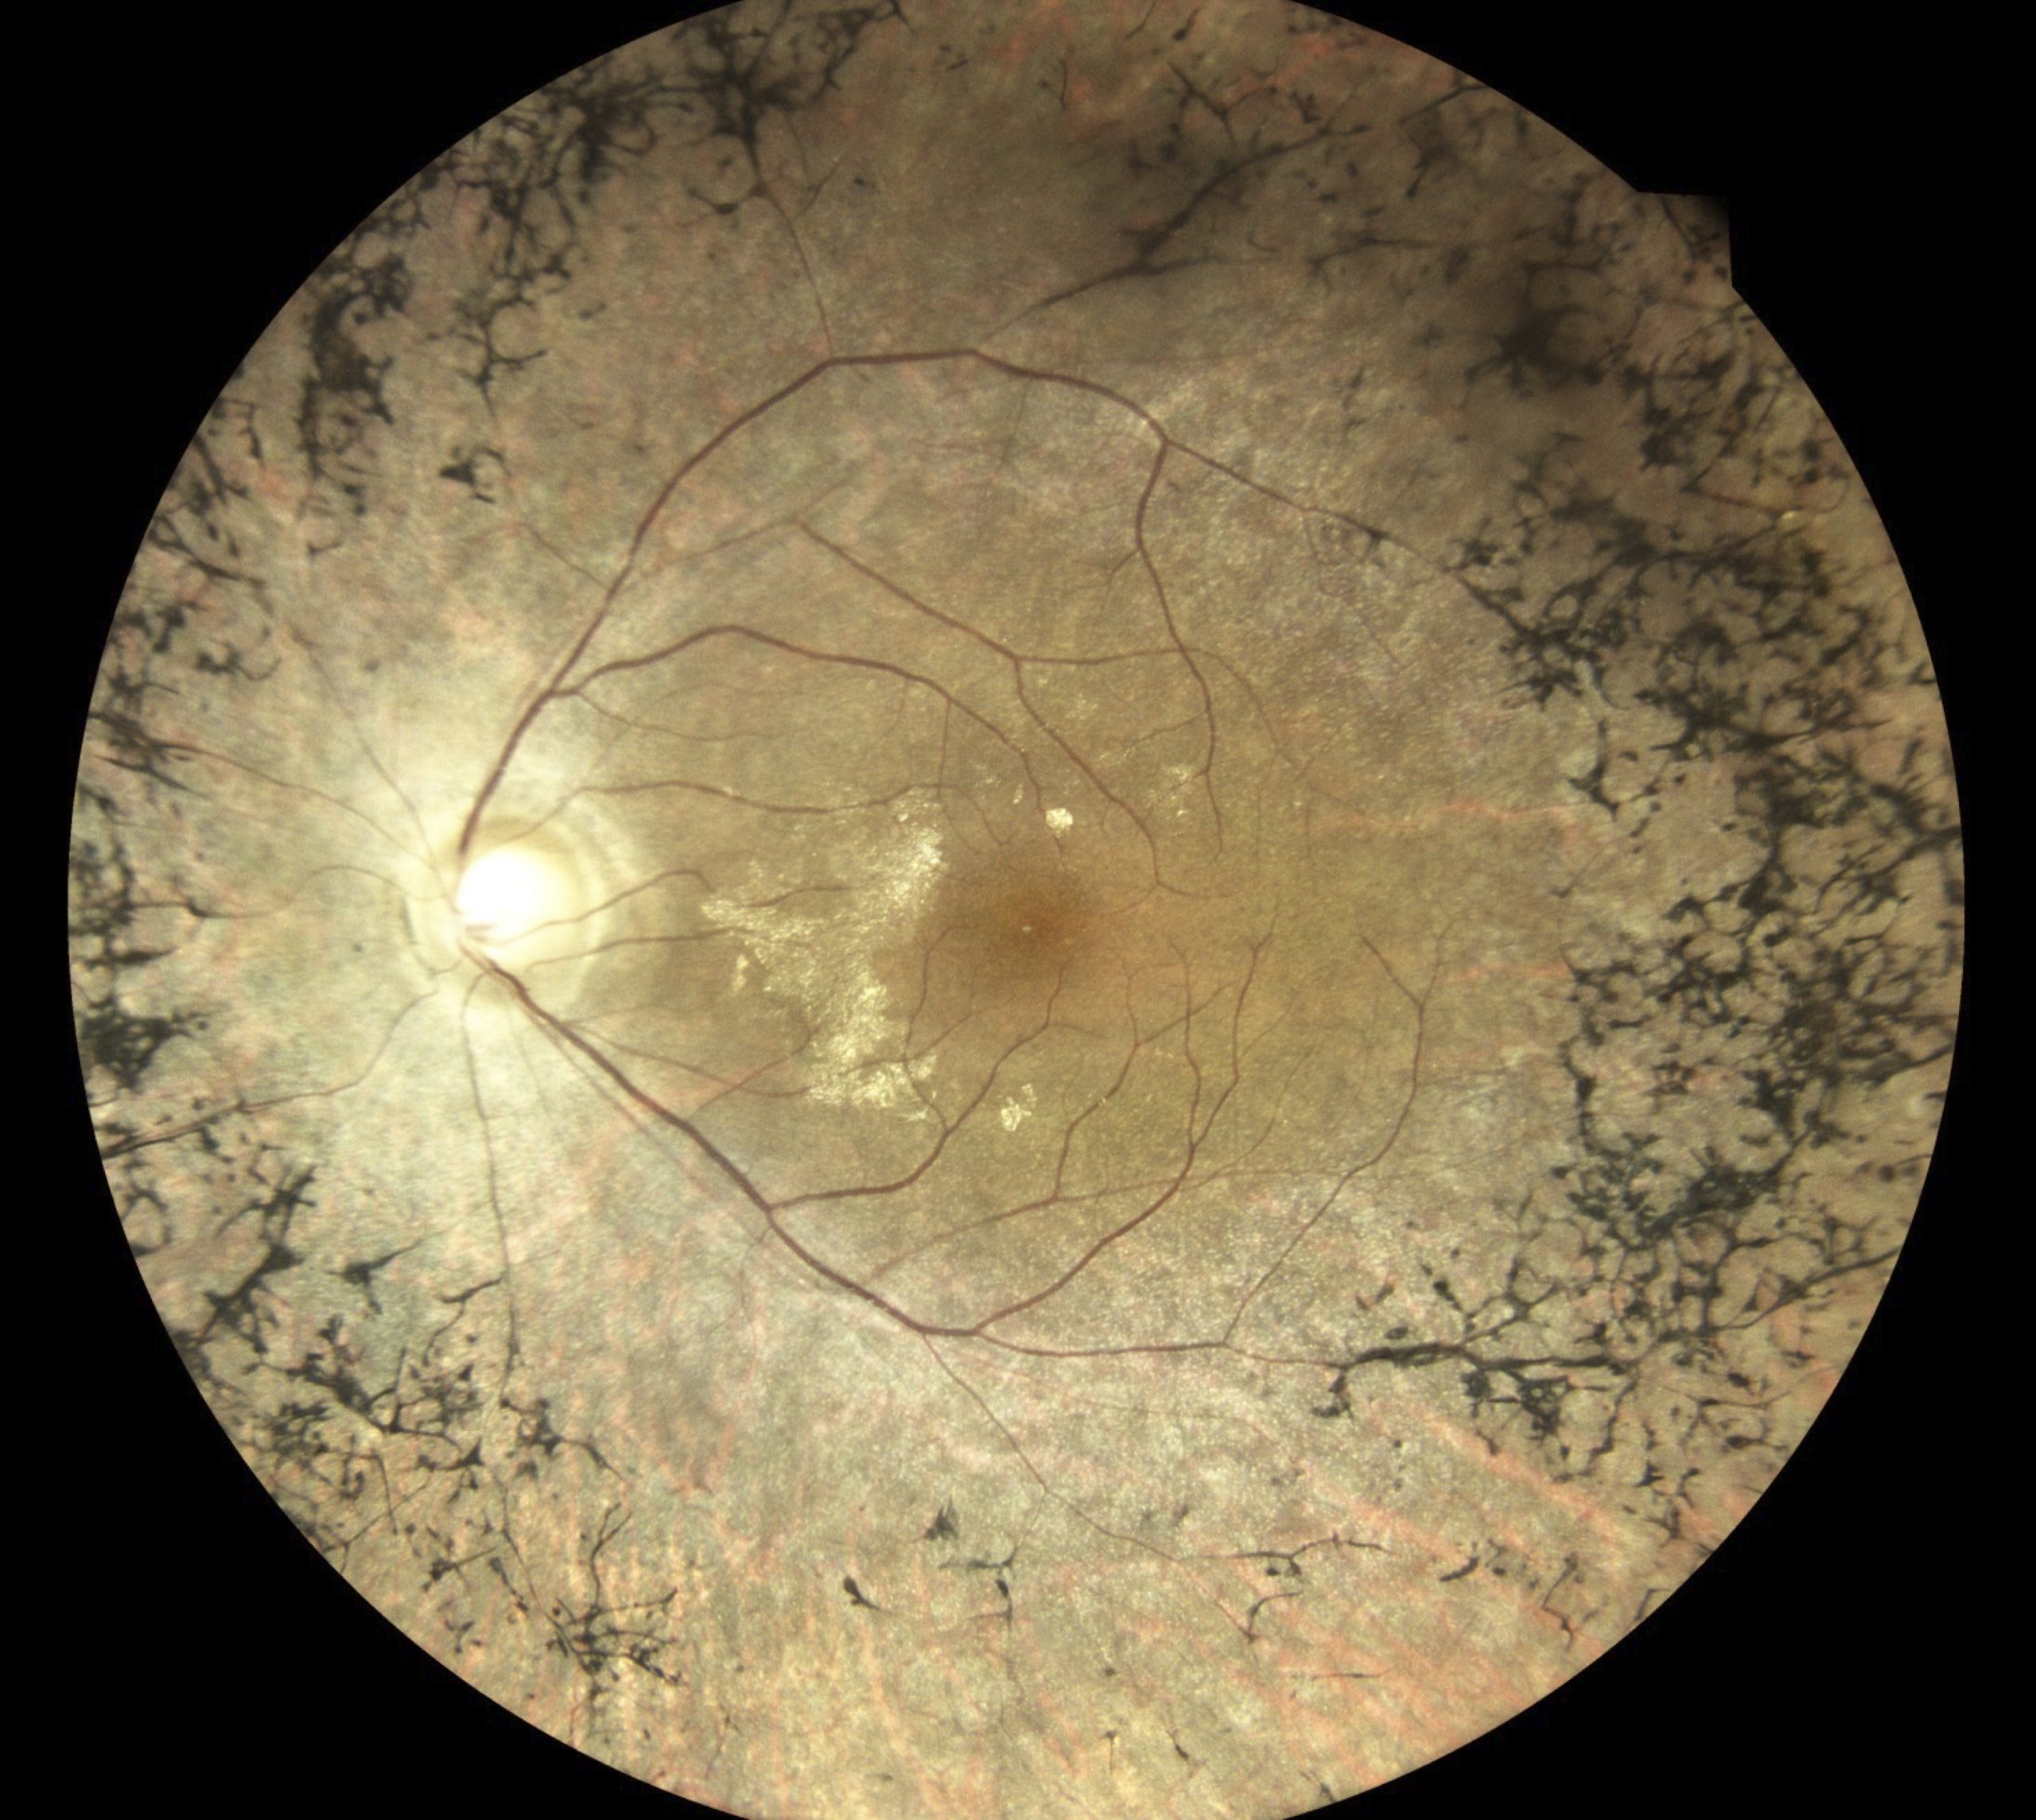

Jeder Augenarzt und jede Augenärztin kennt solche Beispiele aus der Praxis: Ein Patient kommt mit einem Bindehauttumor in die Praxis. Das kann ein harmloser Nävus sein – eine gutartige Fehlbildung wie es auch ein Muttermal ist (Abbildungen 1 und 2). Es kann aber auch ein bösartiger Tumor sein. Deshalb gilt es genau hinzuschauen und den Verlauf zu beobachten: Verändert er sich von einer Untersuchung zur nächsten? Dies lässt sich jedoch ohne eine Fotografie nicht dokumentieren. Ein anderes Beispiel ist das Netzhautscreening bei Menschen mit Diabetes: Sie sollen regelmäßig augenärztlich untersucht werden, um bei Schäden an der Netzhaut rechtzeitig reagieren zu können. Auch hier ist es unerlässlich, bei jeder Untersuchung Fotos der Netzhaut anzufertigen, um Veränderungen im Detail nachvollziehen zu können (Abbildungen 3 und 4).